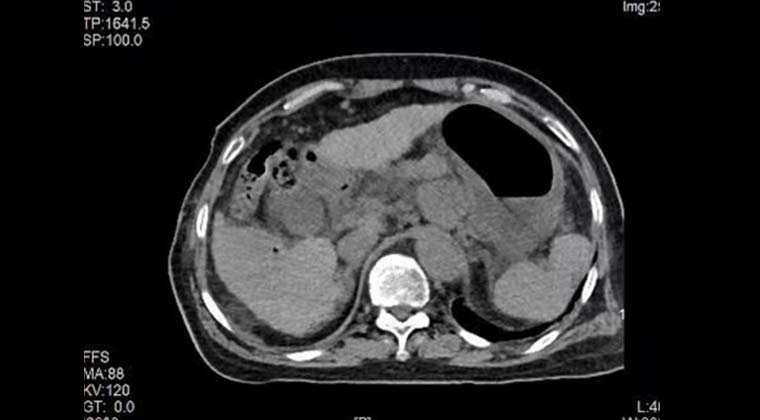

КТ без контраста сразу после процедуры